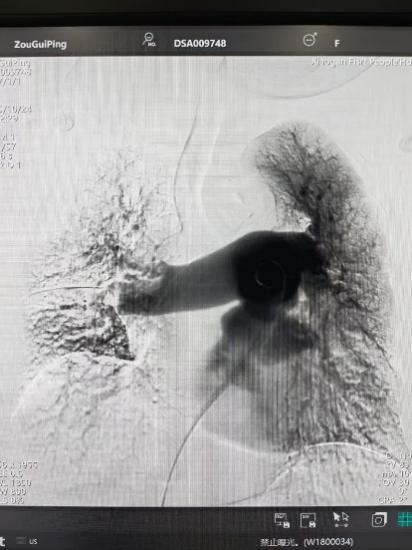

術(shù)后

手術(shù)在局部麻醉下進(jìn)行,團(tuán)隊通過股靜脈穿刺,將專用抽栓導(dǎo)管精準(zhǔn)送達(dá)肺動脈栓塞部位,利用負(fù)壓抽吸技術(shù)成功清除大量血栓;隨后,在血栓局部精準(zhǔn)灌注溶栓藥物,進(jìn)一步溶解殘余血栓,恢復(fù)肺部血流灌注;同時,為防止下肢深靜脈血栓再次脫落引發(fā)肺栓塞,團(tuán)隊為患者置入下腔靜脈濾器,整個手術(shù)歷時約1小時。術(shù)后,鄒婆婆呼吸困難癥狀即刻得到緩解,血氧飽和度顯著提升,右心負(fù)荷明顯減輕,目前身體狀況正在逐步恢復(fù)中。